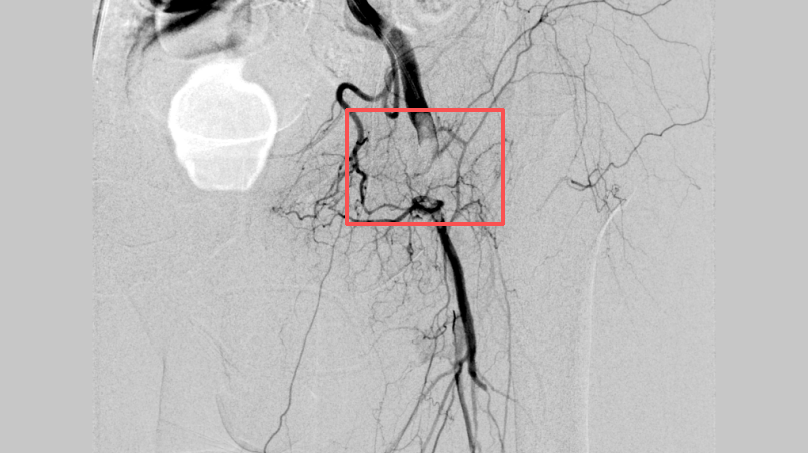

李煒主任帶領團隊通過一個針眼大小的穿刺點,將Rotarex機械血栓抽吸導管精準送達被血栓堵塞的股動脈。隨著設備啟動,大量混合性血栓被粉碎并抽吸出體外,暴露出血管壁原有的狹窄部位。

隨后,對股淺動脈及腘動脈兩處重度狹窄進行切割球囊擴張,血流瞬間恢復通暢。整個手術歷時約2小時,術中造影顯示:堵塞血管全程開通,左下肢血運重建成功。